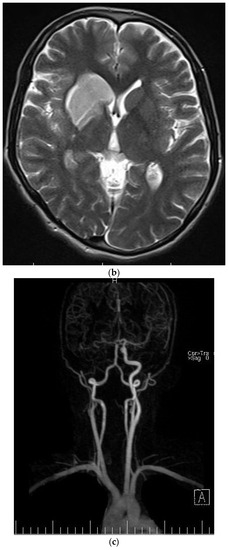

| The current case | 29, female | C2 | CD45, CD43, CD68, S100 | Surgery and radiotherapy | Brain metastasis after 9 months |